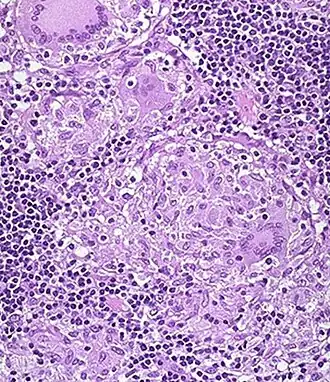

![]() Специфическая гранулёма в стенке толстой кишки. | |

Микроскопически во всей толще кишки находится воспалительный инфильтрат, состоящий из лимфоцитов, плазматических клеток, эозинофилов. Образуются характерные гранулёмы из эпителиоидных клеток и гигантских многоядерных клеток типа Пирогова-Лангханса. Творожистый некроз в гранулёмах не наблюдается, что сближает их с саркоидозными гранулёмами.